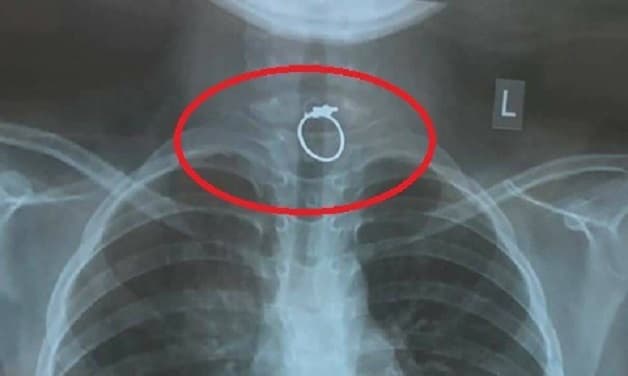

- Hình ảnh chụp x-quang nhẫn mắc trong cổ họng một bé gái